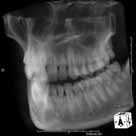

最近のX線画像は解像度が良くなりましたが、それでも従来法である二次元投影法で三次元構造を有する人体を撮影した場合、頬、唇、舌、骨、歯などが重なって描出されてしまい、診断に苦慮する場面が多々ありました。

そこで構造物が重複されずに描出されるCTが歯科でも注目されるようになりました。

CTは最初医科の分野で大きく発展しましたが医科用CTで得られる画像は歯科口腔領域には向いておらず解像度も落ちてしまいます。

そこで当院では歯科医療分野の中で最も画像解像度が高いとされる歯科用CT(CBCT)を導入しています。

volumeをXYZ方向にそれぞれ512分割しておりこのときのスライスピッチは標準モード撮影で147㎛、高解像度モード撮影(ハイレゾ)で101㎛です。 3D画像はリアルタイムで自由に動かすことができるので骨の形態や奥行きを容易に把握できます。 さらにウィンドウレベルを操作することでさまざまな画像を簡単に得ることができます。 またインプラント治療においては下顎管やオトガイ孔、上顎洞下壁までの距離を正確に測定できるので術中も安全に治療をおこなうことができます。 |